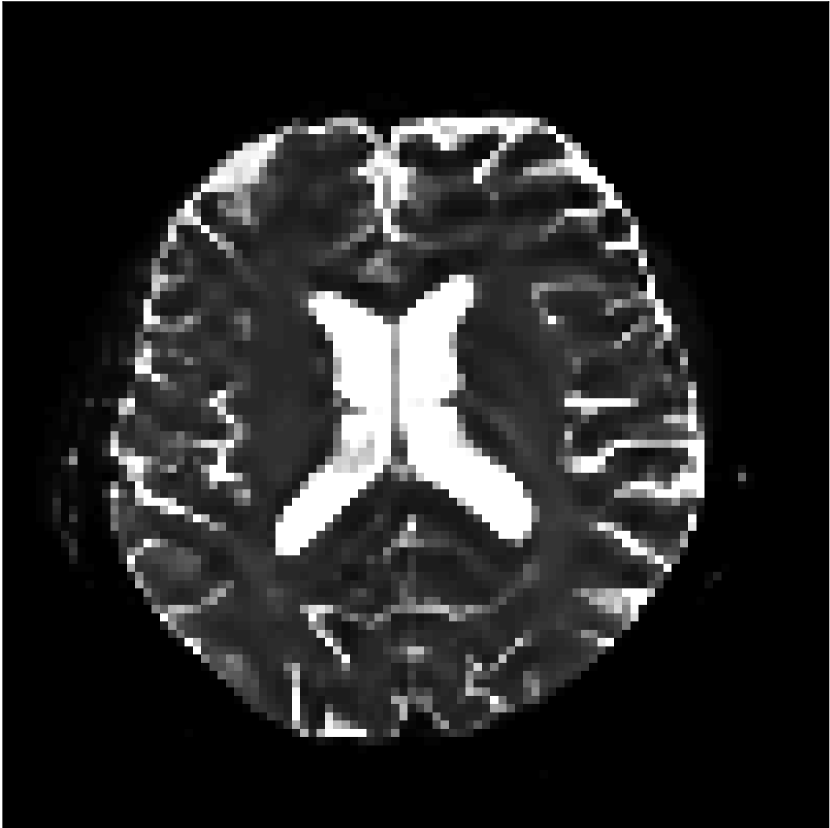

Figure 9 shows parameter maps for the different methods without partial Fourier (No PF) and with 5/8ths partial Fourier (5/8 PF). Mean diffusivities calculated from the raw DWI data (Raw) show notable noise and Gibbs ringing artifacts, while this is substantially removed with the state-of-the-art (SoA) method. However, the state-of-the-art method begins to lose its ability to compensate for the Gibbs ringing and resolution loss when partial Fourier is utilized in the acquisition. The effects of partial Fourier increases are primarily evident in the enlargement of the lateral ventricles and the presence of black lines in the vicinity of the lateral ventricles. The MCNN model is able to compensate somewhat for the ringing effects, but begins to introduce substantial artifacts at the 5/8ths partial Fourier factor, whereas the CCNN model continues to give high-quality mean parameter maps across all PF factors.

Raw

SoA

MCNN

Standard PF

CCNN

b=0𝑏0b=0 s/mm2

No PF

MD, μ𝜇\mum2/ms

5/8 PF

FA

MK

Figure 9: Parameter maps from various methods (with CSF masks for FA and MK). At the top are shown the b=0𝑏0b=0 images from Raw, state-of-the-art (SoA), MCNN, standard partial Fourier, and CCNN methods. Rows 2 and 3 show results for mean diffusivity, rows 4 and 5 show results for fractional anisotropy, and rows 6 and 7 show results for mean kurtosis. The SoA method and both deep learning methods perform well without partial Fourier acceleration; however, at the 5/8ths partial Fourier factor, substantial artifacts are present for all methods other than the CCNN method.

Similar trends are observed in the other diffusion parameter maps.